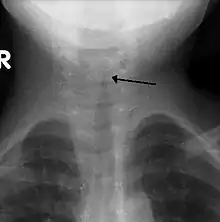

Croup (Laryngotracheobronchitis) is a viral infection of the vocal cords typically lasting five to six days. The main symptom is a barking cough and low-grade fever. On an X-ray, croup can be recognized by the "steeple sign", which is a narrowing of the trachea. It most commonly occurs in winter months in children between the ages of 3 months and 5 years. A severe form caused by bacteria is called bacterial tracheitis.[12]